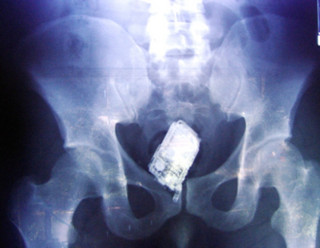

Γιατί ορισμένοι άνθρωποι πραγματικά έχουν περίεργες διατροφικές συνήθειες. Ιδού στις παρακάτω ακτινογραφίες τι απίθανο βρέθηκε στα στομάχια ορισμένων απρόσεκτων ή μη.

Κινητό